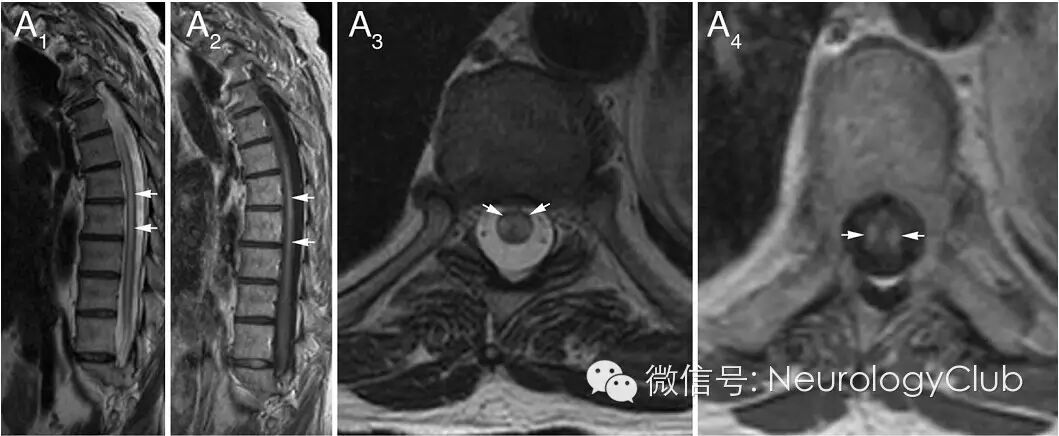

(A1:T2WI异常信号超过7个节段;A2:病灶强化;A3:横断面T2WI对称异常信号;A4:病灶强化)